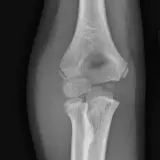

Over 2,100 interactive radiology cases, curated by radiologists for your level of training. Scroll, window, and view cases full screen — just like on PACS. Click linked findings in each writeup to jump straight to them on the image. Cases include sample reports, a focused discussion section, original illustrations, and videos.

完全交互式病例,配备您在 PACS 上期待的各项工具——滚动、调窗、缩放、平移、测量、ROI 和全屏模式。

丰富的标注直接在病例图像上突出关键发现。点击病例讲解中的关联发现,即可跳转至其在扫描上的精确位置。